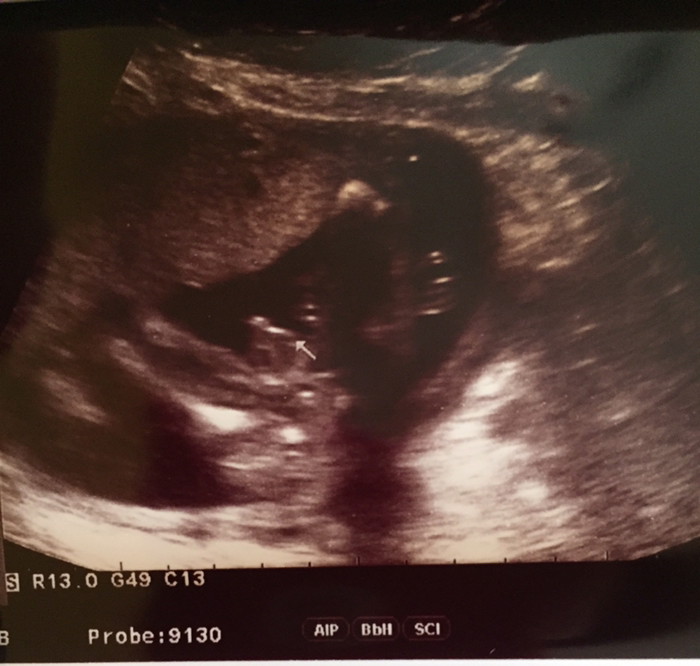

ซาวด์ตอน 14wค่ะ 😊